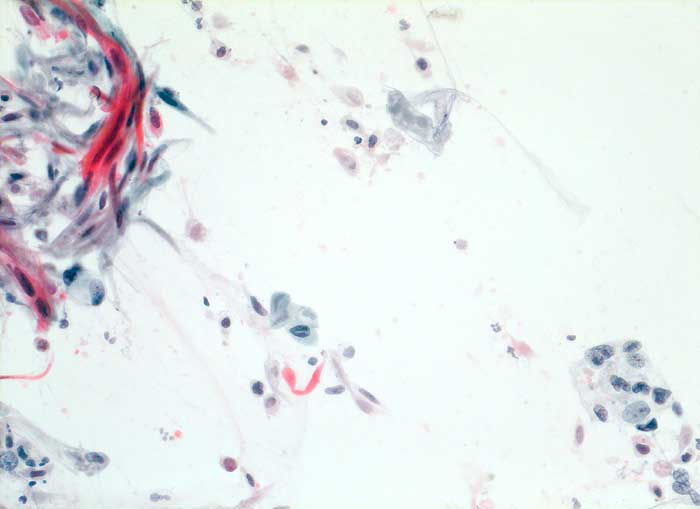

PathoPic – image database / PathoPic ID 5723 - Verhornendes Plattenepithelkarzinom

Verhornendes Plattenepithelkarzinom

maligner Tumor

Sputum

Lunge, Mediastinum mit Thymus

Histologische Diagnose: wenig differenziertes verhornendes Plattenepithelkarzinom

Zytologische Diagnose: verhornendes Plattenepithelkarzinom mit entdifferenzierten Anteilen.

Die Karzinomdiagnose gründet hauptsächlich auf den unverhornten Zellen, die Diagnose des Karzinomtyps auf den keratinisierten Zellen (Papanicolaou: rot). Die unverhornten Zellen lassen auch an ein Adenokarzinom denken.

Die Karzinomdiagnose gründet hauptsächlich auf den unverhornten Zellen, die Diagnose des Karzinomtyps auf den keratinisierten Zellen (Papanicolaou: rot). Die unverhornten Zellen lassen auch an ein Adenokarzinom denken.

Zytologie

200